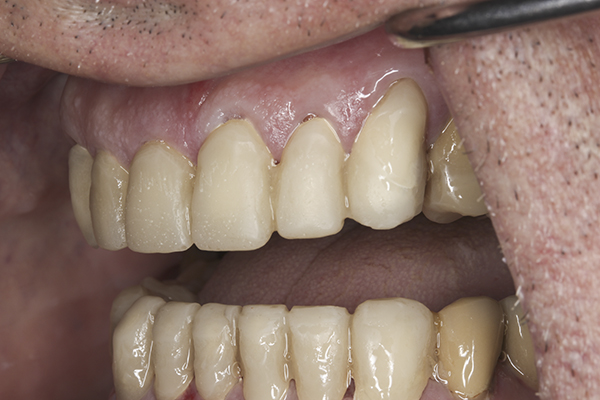

(32.) Postoperative right lateral, open view.

Figure 32

(33.) Postoperative anterior, open view.

Figure 33

(34.) Postoperative left lateral, open view.

Figure 34